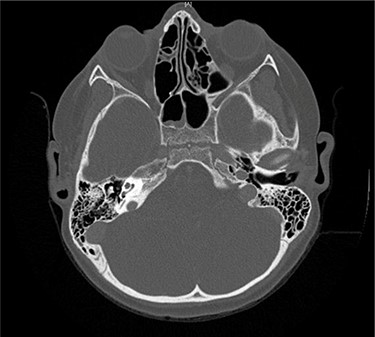

Serial MRIs were conducted following discharge. MRI at 1 month showed a contrast-enhancing mass in the right internal auditory canal with enhancement of the right petrous apex and associated labyrinthitis. An MRI at 2 months showed persistence of the lesion, whereas computed tomography (CT) showed new osseous erosion and irregular lucency within the posterior cortex of the petrous apex (Figs 1 and 2). Given the patient’s hearing loss, persistence of the lesion and concern for neoplasm, surgical intervention was recommended to the family. Surgery was initially deferred, and serial imaging was recommended. The facial nerve palsy resolved and patient was followed closely as outpatient with family reluctant to pursue surgical intervention. However, repeat imaging at 4 months after the initial encounter demonstrated persistence of the lesion, and the family consented to surgery.

Axial CT taken 2 months after initial presentation demonstrates lucency of the right petrous apex representing partial pneumatization, as well as osseous erosion of the posterior cortex.